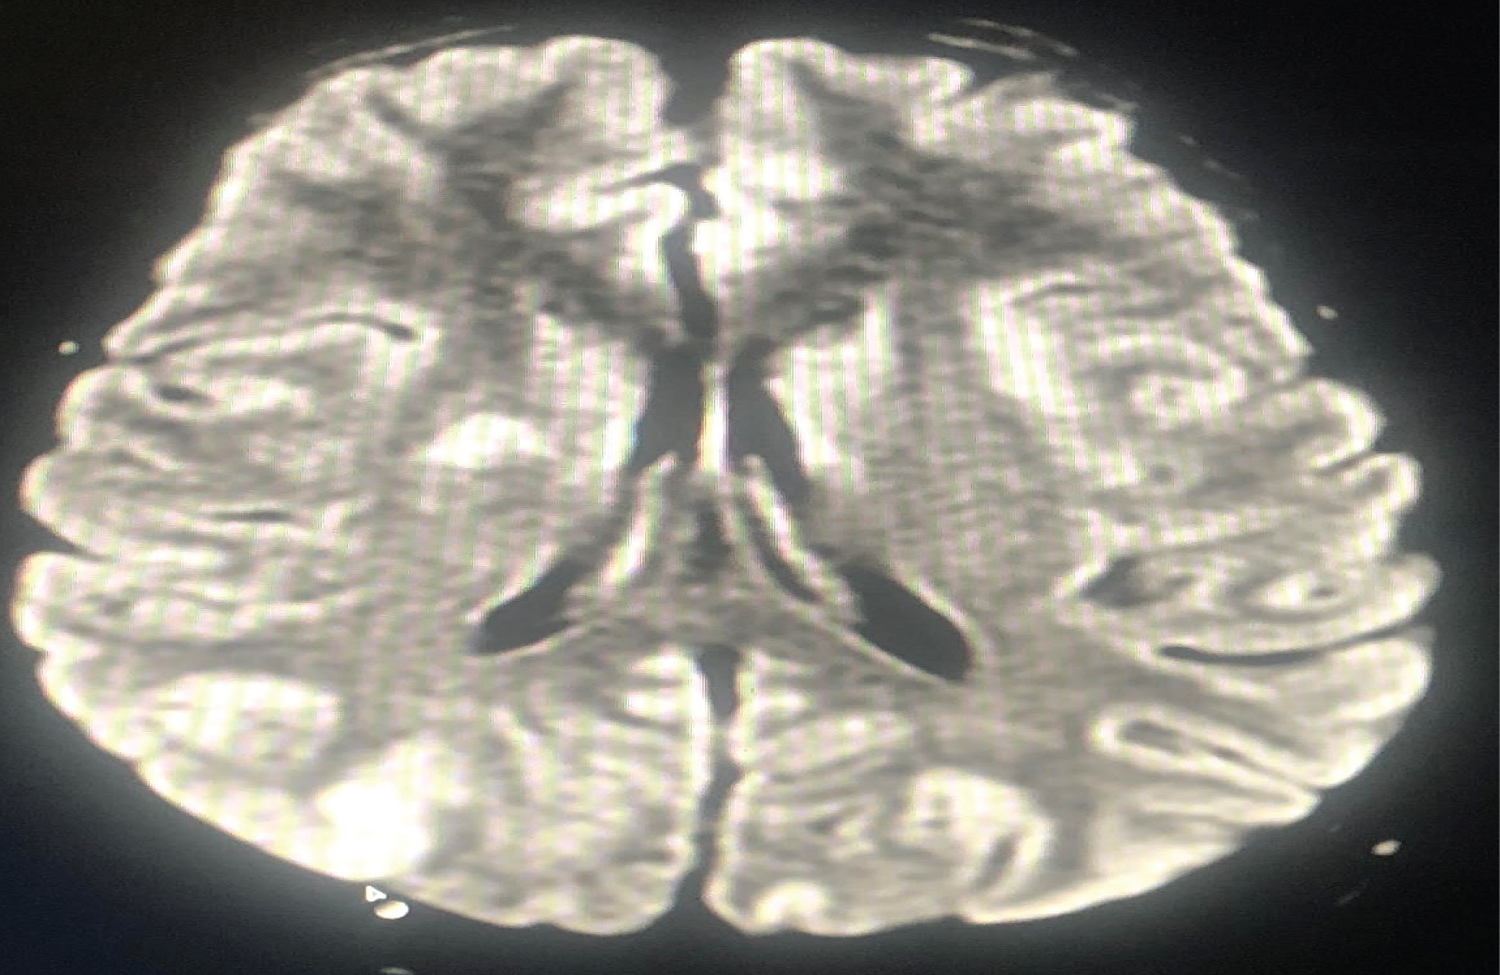

The first patient, a 20-year-old woman who underwent a caesarean section under spinal anaesthesia complained of a headache immediately after surgery and experienced a generalised tonic-clonic seizure 4 hours later. Vitals remained stable. Supplemental oxygen, midazolam, magnesium sulphate, levetiracetam, mannitol, furosemide, and steroids were used to treat the patient. The results of a brain MRI showed subcortical vasogenic edoema suggestive with PRES and bilaterally symmetrical areas of altered signal intensity in the fronto-parieto-occipital and right basal ganglia. Within 4 days, the patient had improved (Figure 1 and Figure 2).

Figure 1: MRI Brain depicting areas of altered signal intensity in right basal ganglia region. View Figure 1